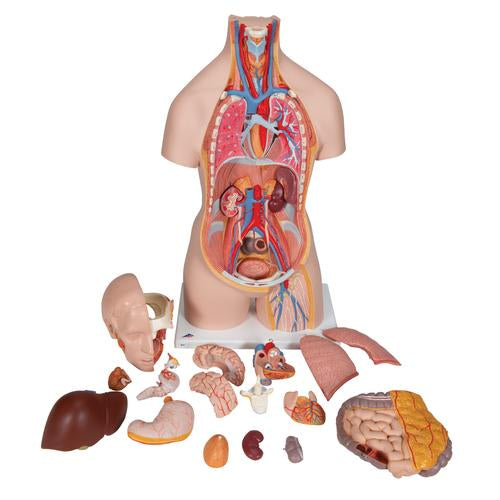

This meticulously crafted torso is expertly hand-painted with precision and made from high-quality plastic. All 3B torsos are designed and produced in Germany. This unisex human torso model features a distinctive open neck and back section extending from the cerebellum to the coccyx. It accurately depicts vertebrae, intervertebral discs, spinal cord, spinal nerves, vertebral arteries, and numerous other components in this vibrant representation of human anatomy. This human torso model includes the following detachable parts and organs:

- Removable 7th thoracic vertebra

- 6-part head

- Pair of lungs

- 2-part heart

- Stomach

- Liver with gall bladder

- 2-part intestinal tract

- Front section of kidney

- Front section of urinary bladder

Each organ in this human torso is hand-painted to ensure a high-quality product. This exceptional educational tool for human anatomy simplifies learning the placement of human organs. It is a